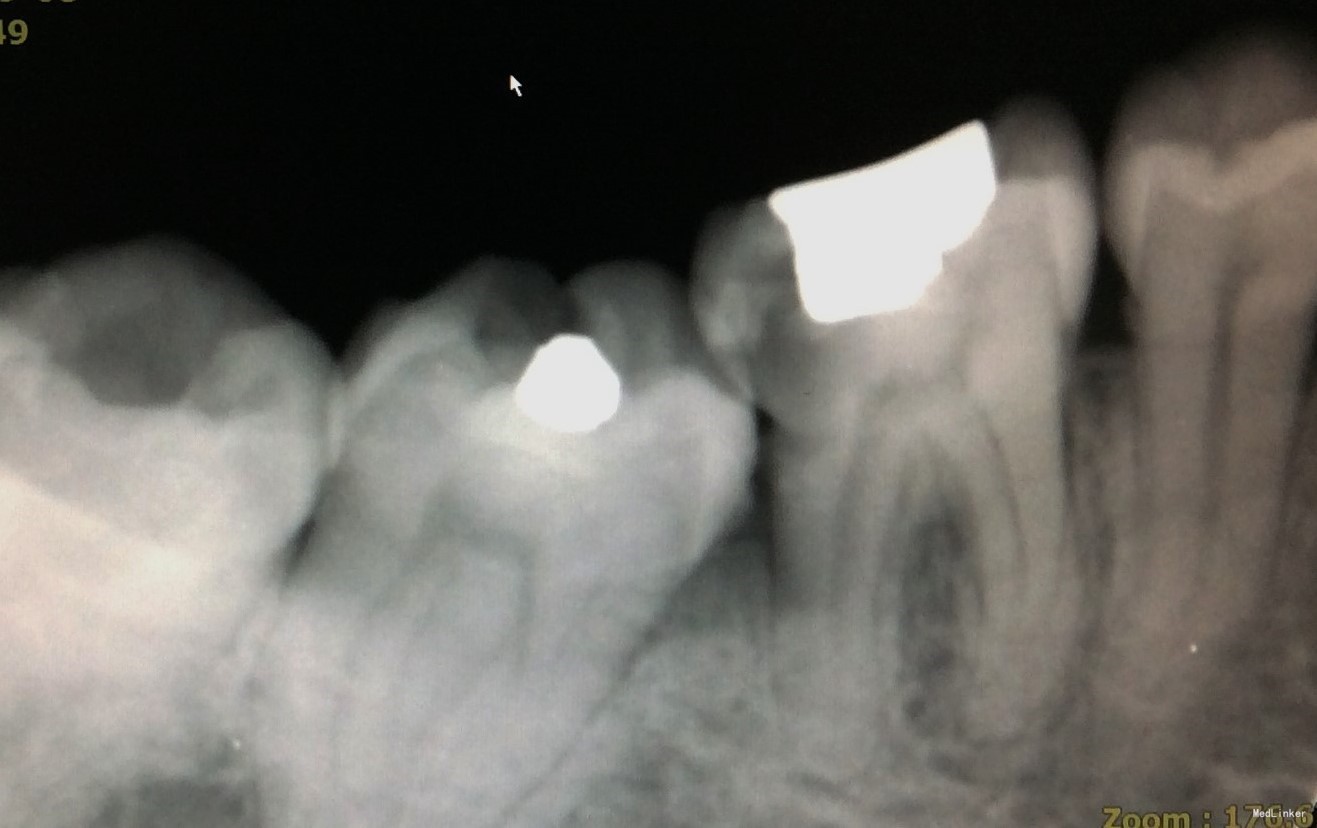

首次复诊:46牙上橡皮障,揭全随室顶,显微镜下探查根管口,3根管牙,清理髓腔,#08,#10,#15不锈钢K锉疏通根管,根测仪测量根管长度,近颊根19mm,近舌根18.5mm,远中根20mm;EDTA润滑剂作用下,机用镍钛器械Protaper清扩至#2506锥度,远中根#3004,K锉疏通至#40;示尖到位;超声荡洗,次氯酸钠冲洗,干燥,根管内封氢氧化钙,髓腔置干棉球,CAVITON暂封。

1、下颌第一磨牙3根管最常见,上图清晰展示了开髓后根管口的分布。寻找根管口应注意寻找是否有远舌根,因为远舌根通常位置靠近远中边缘,若随室顶没揭全,易遗留。